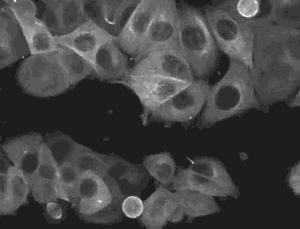

8.上皮细胞有丝分裂。有丝分裂是细胞核分裂的过程.通过有丝分裂,每条染色体精确复制成的两条染色单体均等地分到两个子细胞,使子细胞含有同母细胞相同的遗传信息。